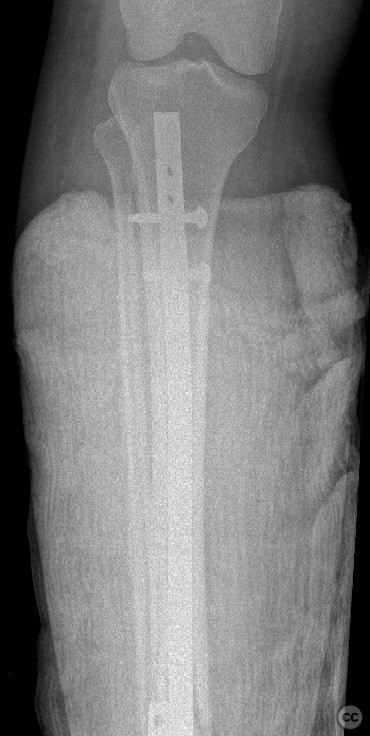

Planning remarks:  The preoperative plan included a staged approach: initial stabilization of the tibial shaft fracture with an intramedullary nail via an infrapatellar approach, followed by open reduction and internal fixation of the trimalleolar ankle fracture through separate medial and posterolateral incisions.

The combination of ipsilateral tibial shaft and trimalleolar ankle fractures presents technical challenges in maintaining alignment and stability during fixation. Sequential fixation allowed for restoration of tibial length and rotation prior to addressing the articular surface of the ankle. Careful soft tissue handling was required due to the proximity of multiple incisions. Stable fixation of all malleolar fragments was achieved with lag screws and neutralization plating as indicated.

Orthopaedic implants used:   tibial intramedullary nail; 3.5mm tubular plate; 4.0mm cannulated screws; mini plate, k wire, cerclage